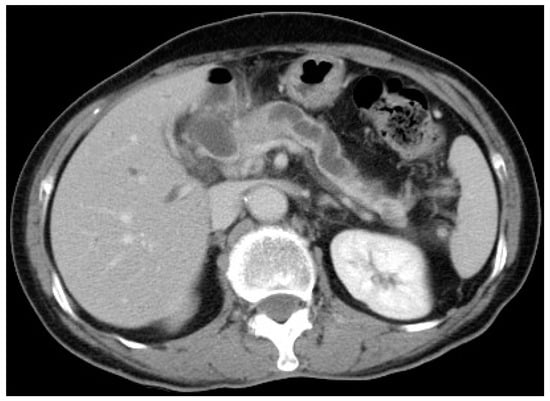

6.2. Endoscopic Ultrasound

- Heinzow, H.S.; Kammerer, S.; Rammes, C.; Wessling, J.; Domagk, D.; Meister, T. Comparative analysis of ERCP, IDUS, EUS and CT in predicting malignant bile duct strictures. World J. Gastroenterol. 2014, 20, 10495–10503. [Google Scholar] [CrossRef]